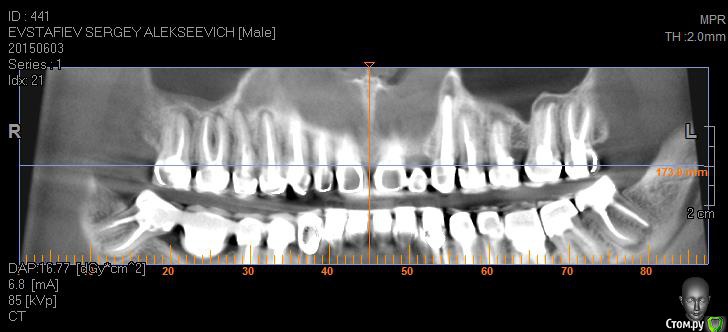

Evstafjev Опубликовано 25 октября, 2015 Поделиться Опубликовано 25 октября, 2015 (изменено) Здравствуйте уважаемые форумчане! Возможно пишу не в ту ветку форума, но мне кажется что эта самая близкая.Приключилось со мной настоящая беда. Расскажу по порядку.Лет 5 назад в виду совсем плохой ситуации с зубами мне предложили и воплотили следующую методику лечения: депульпировали все зубы и покрыли металлокерамическими коронками. Каналы пломбировали гутаперчей, и укрепили титановыми штифтами. Я был безмерно счастлив. Во первых что через все это "прошел" во вторых что стал нормальным человеком с красивой улыбкой и с возможностью "жевать полным ртом".Но с одним зубом у меня всетаки возникла проблема. Года через 2 после лечения заболел сильно верхний 5-й зуб. Я пошел к врачу, ничего особого не заметили и сказали пропить курс антибиотиков а потом придти снова. Я пропил, зуб прошел, плюс обстоятельства сложились, и я не пришел к врачу. Все было хорошо. Но через какое то время (довольно продолжительное) я заметил небольшую шишечку у проблемного зуба на десне. Это оказался свищ. Абсолютно не беспокоил, поэтому я его не сразу и заметил. Этим летом, в виду переезда на постоянное место жительство в другой город, я решил что нужно перед отъездом решить вопрос с зубом. Пошел к врачу, там посовещались и решили что дабы не разбирать конструкцию попробуют сделать резекцию верхушки корня. Отправили на КТ. Сделал КТ 5х5 и увидел что у соседних зубов на корнях также "шишки". Испугавшись сделал КТ всей полости, и о ужас..... на каждом зубе есть такие же "шишки"!!! Прилагаю снимки сделанные из программы КТ, так как все содержимое диска с КТ сюда не поместить, если только через файлообменник, но объем большой и врятли кто то захочет скачивать.Врачи толком ничего не говорят. Сами озадачены. Сказали что раз картина тотальна то то что они плохо пролечили исключено, а что это реакция организма. Решили пока в качестве эксперимента пролечить через канал проблемный 5-й зуб. Протезист сказал что штифты выкручиваются без проблем. Распилил коронку вывернул штифт и далее терапевт начал лечение используя физиопроцедуры с током. Лечили 2-3 месяца. Запломбировали гутаперчей и закрыли временной пломбой. Сказали нужно хорошенько подождать чтобы понять помогло ли лечение. Вот на днях будут смотреть что вышло.Подскажите уважаемые специалисты, каково Ваше мнение по ситуации. Так прискорбно понимать что я в 36 лет похоже лишился всех зубов...PS:Пока лечили зуб параллельно у меня заболели зубы на нижней челюсти. Делали разрез, пил антибиотики - кошмар. Изменено 25 октября, 2015 пользователем Evstafjev Ссылка на комментарий

Evstafjev Опубликовано 26 октября, 2015 Автор Поделиться Опубликовано 26 октября, 2015 Я вот думаю что фото из КТ не полностью показывают картину, не очень я владею данным программным обеспечением, с трудом поймал ракурс. Но не очень информативно. Если крутить мышкой отдельно у каждого зуба тот там картинка "пострашнее" Ссылка на комментарий